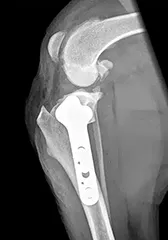

Tibial Plateau Levelling Osteotomy

What is a TPLO?

So why choose TPLO?

- The cranial tibial thrust force is very large and it often overcomes the restraint provided by the over-the-top or lateral fabello-tibial suture techniques.

- In our experience dogs that have had TPLO will walk on the operated leg much sooner than those that have had the over-the-top or lateral fabello-tibial suture techniques

- Heavy/boisterous dogs or dogs with bilateral cruciate ligament ruptures/other orthopaedic disease tend to put a lot of their weight on the operated leg very soon after surgery. TPLO has two advantages in this regard:

- It is strong enough to allow immediate but controlled weight-bearing

- Dogs are comfortable enough to stand and walk on the operated leg very soon after surgery (more often than not within 24-48 hours)